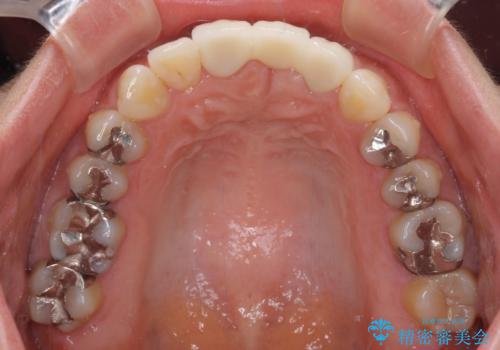

- 接着タイプの前歯のブリッジが不自然であるとのことで来院された患者様です。

欠損部の歯肉が窪んでいるため、歯肉移植により形態を改善し、オールセラミックブリッジにて補綴することとしました。

事前に装着されていた接着タイプのブリッジは、歯の切削量が少ない反面、接着界面から虫歯が進行しやすく、脱落リスクが高くなるというデメリットがあります。